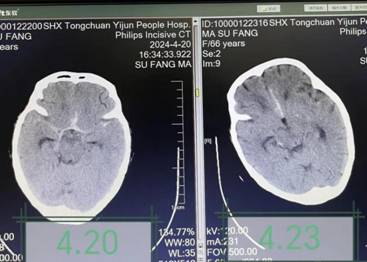

拟行姑息治疗。了解病情后,医疗团队详细查阅患者病历资料,认真细致查体,患者生命体征不平稳,深昏迷状,疼痛刺激无反应,颈项强直。经讨论分析,患者突发昏迷的原因可能为再出血及脑血管痉挛,同时存在代谢性酸中毒、肺炎、电解质紊乱等影响脑功能,充分评估后,团队建议进行腰椎穿刺及脑脊液置换术。经与家属详细沟通,征得同意后连夜安排手术。手术由神经内科主治医师李妮妮操作,术中可见血性脑脊液流出,经多次脑脊液置换,脑脊液血色逐渐变淡,约半小时顺利结束手术。术后继续给予止血、营养神经、抗感染、纠酸、呼吸支持等综合治疗。在医护人员的精心照料下,次日查房患者意识转清,头痛症状明显缓解,能够与家属及医护人员正常交流,四肢活动也有明显恢复,复查颅脑CT显示出血及水肿情况较前减轻。经过3天巩固治疗,患者病情基本稳定。面对患者奇迹般的恢复,家属对治疗团队的敬业精神和高超医术表示惊叹及深深的感谢。

治疗前后颅脑CT对比,颅脑水肿及出血减轻